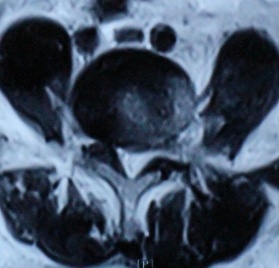

2. 患者董某,女,70岁,因“腰部疼痛并右下肢疼痛、麻木1年余,加重10天”入院。入院前曾多次行针灸、理疗、骶管封闭等治疗,经治疗后病情复发。入院见患者腰痛并右下肢疼痛,双足麻木,间歇性跛行,跛行距离约50米。查:直腿抬高试验右30°阳性,右踇背伸肌力、腓骨长短肌肌力Ⅲ级,双小腿外侧、足背皮肤感觉减退,右侧为甚。入院后诊断为腰椎间盘突出症。患者既往患高血压、冠心病、慢性胆囊炎、胆结石病史,形体肥胖。入院后完善检查,明确诊断,请相关科室会诊后认为手术风险大且患者形体肥胖,为手术增加难度,势必延长手术时间,增加手术风险。经科室讨论后行经皮椎间孔镜下髓核摘除,手术麻醉方式为局麻。入院后第三日手术,经椎间孔入路椎间孔镜下髓核摘除椎管扩大成形术。手术顺利,术中无出血,手术时间约1小时。术中可与患者交流。术后患者即可感右下肢无疼痛,第二天佩戴腰围下地活动后双下肢无不适。术后第三天出院,术后第三天复查腰椎MRI示突出髓核已摘除,神经根无受压。术后随访三月,患者目前病情恢复良好,无下肢疼痛。

术后第三天腰椎MRI